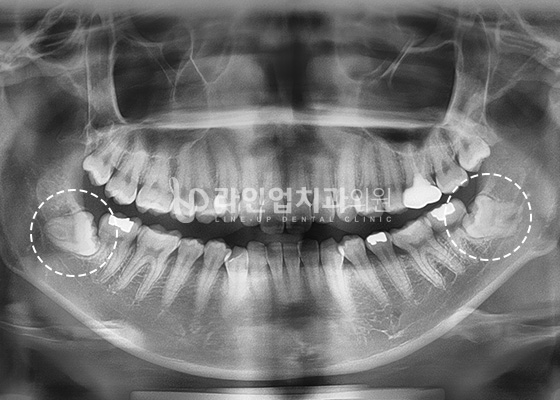

Case of Wisdom Tooth Extraction

Before

After